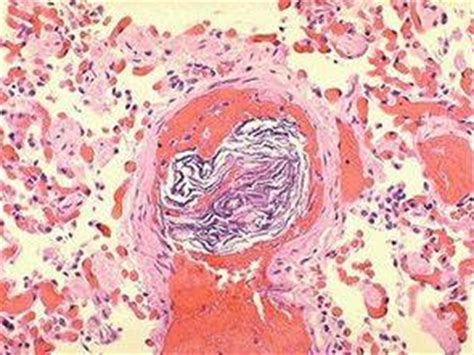

栓塞就是小的固体或是液滴、气泡进入血液循环堵塞血管的现象。羊水栓塞指的是羊水中的有形成分,比如胎儿脱落的上皮、胎粪等进入母亲血液循环引起的并发症。

在子宫收缩过强、子宫出现损伤的时候,羊水中的成分比较容易进入母亲的血液,发生羊水栓塞。羊水栓塞危害很大,首先这些栓子会堵塞血管,最有可能会堵塞肺部的血管,造成肺栓塞,而如果肺栓塞,人体的氧气供应就会受阻。羊水栓塞比血栓等栓塞更危险的地方在于,来自胎儿的成分是异体成分,不仅会堵塞血管,还会引起免疫反应,可导致过敏性休克。不仅如此,怀孕期间母亲的血液处于高凝状态,而羊水中又含有许多促凝物质,因此二者相遇就容易发生弥漫性血管内凝血(DIC),这样不仅会产生大量微血栓,还会一下子消耗太多凝血因子,纤溶系统也被激活,此后血液就会变得无法凝固止血,引起产后出血甚至出血性休克。而人在休克状态,还可以出现器官功能的衰竭。